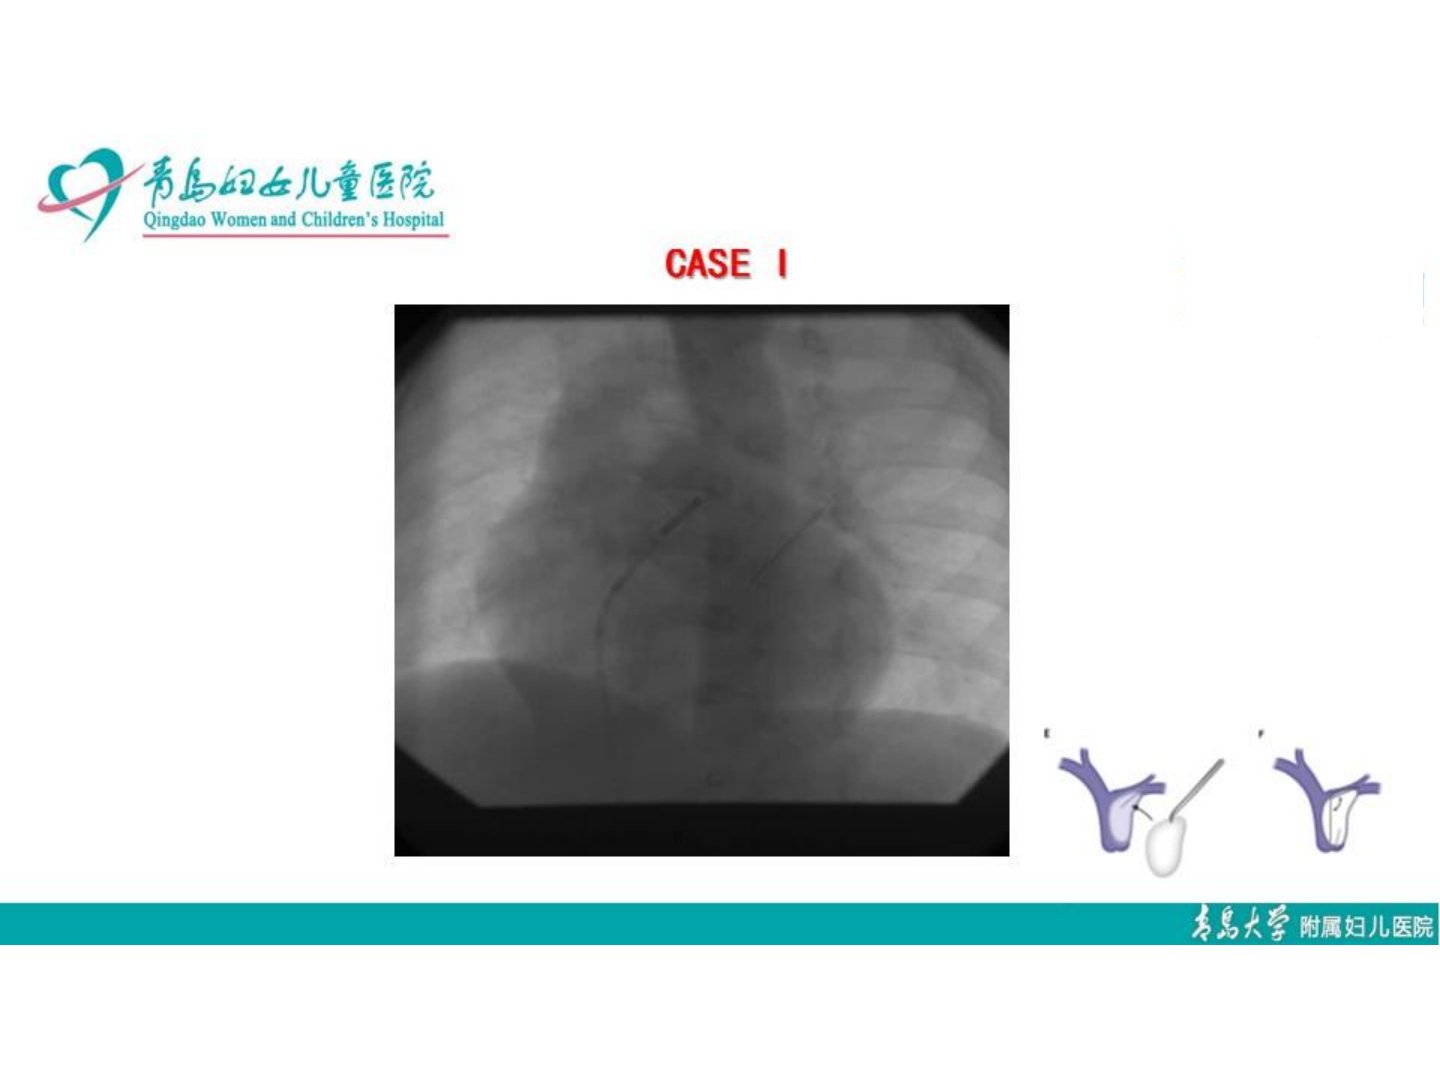

肺动脉分支术后再狭窄治疗策略再思考摘要肺动脉分支术后再狭窄是临床治疗面临的棘手问题严重影响患者预后需重新审视其治疗策略。术后再狭窄病因复杂涉及手术操作、血管自身特性及血流动力学改变等多方面因素。传统治疗手段如再次手术、球囊扩张等虽能一定程度上缓解症状但存在创伤大、再狭窄风险高等局限。近年来新型治疗方式不断涌现。药物涂层球囊可抑制内膜增生降低再狭窄几率;支架置入术能提供持续支撑维持血管通畅。此外基因治疗、干细胞治疗等前沿技术也展现出一定潜力通过调节血管内皮功能、促进血管修复来改善病情。临床治疗需综合考虑患者个体情况包括年龄、基础疾病、再狭窄程度等制定个性化方案。同时加强术后随访与监测早期发现再狭窄迹象并干预对于提高治疗效果、改善患者生活质量至关重要。